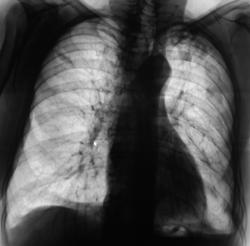

Пациент находится на диспансерном учете в туб. кабинете, по поводу инфильтративного туберкулёза верхней доли левого лёгкого, получает специфическое лечение. Пациент направлен в рентгеновский кабинет для рентгенологического исследования исследования органов грудной полости "в динамике". Проведено стандартное исследование.

Для сравнения приводятся изображения, произведенные чуть больше года тому.